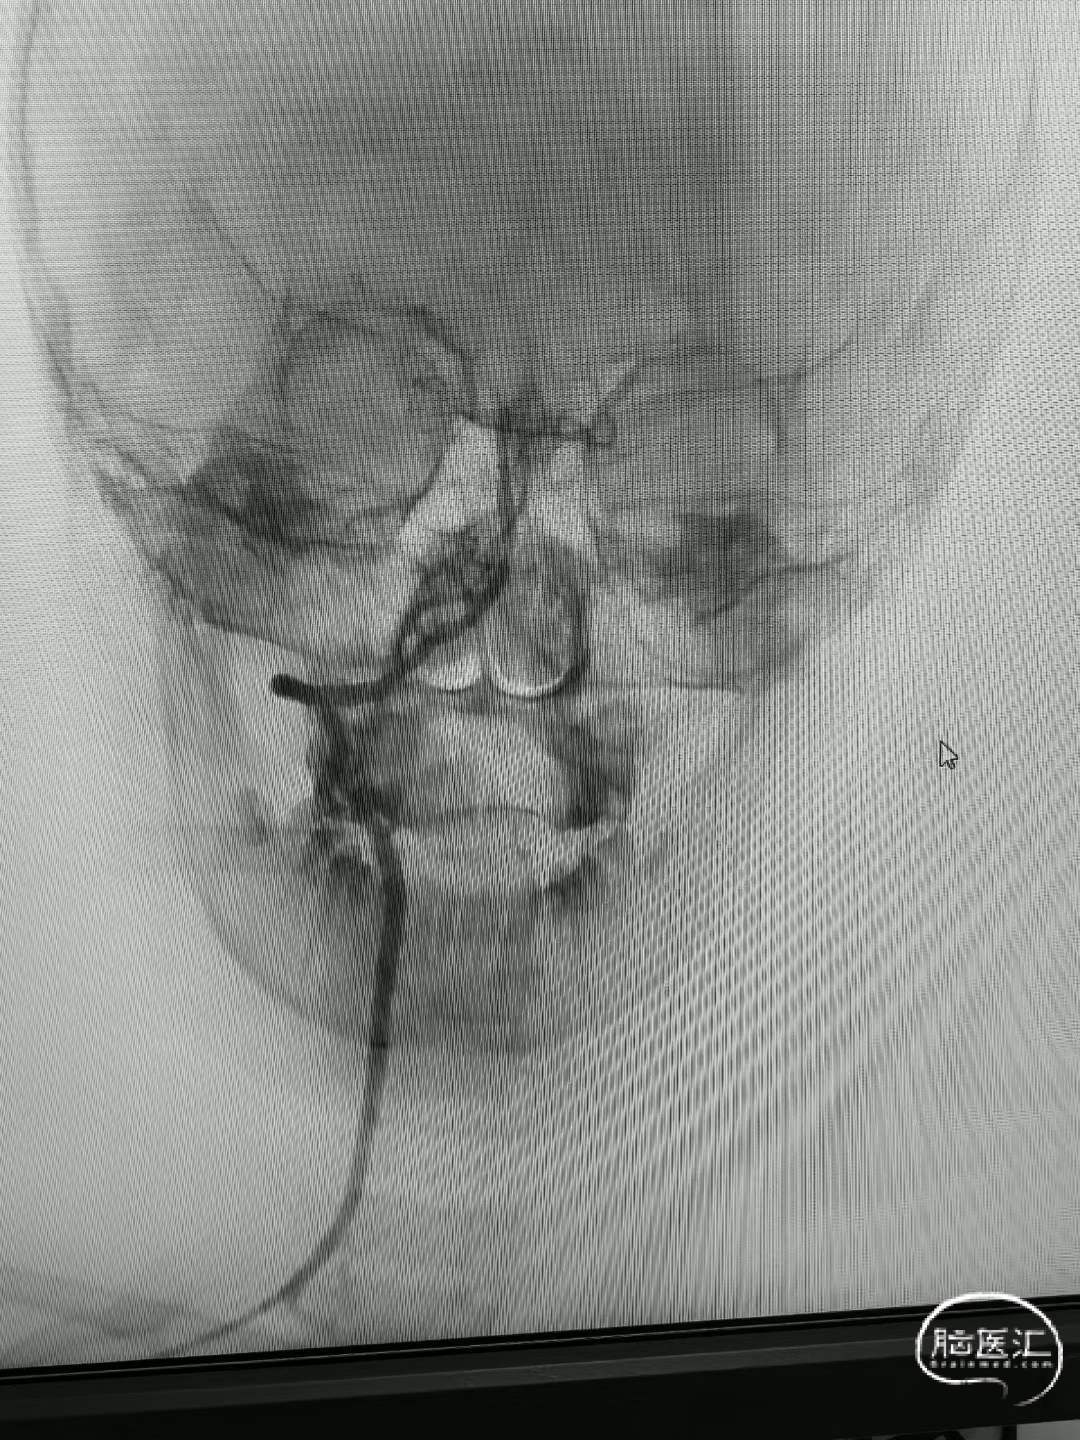

经肱动脉建立通路,抽吸,支架取出部分血栓,但考虑病变性质是夹层,血流无法维持,放置支架后基底动脉完全再通。

524645a2d26724318e896a347426d700.jpg